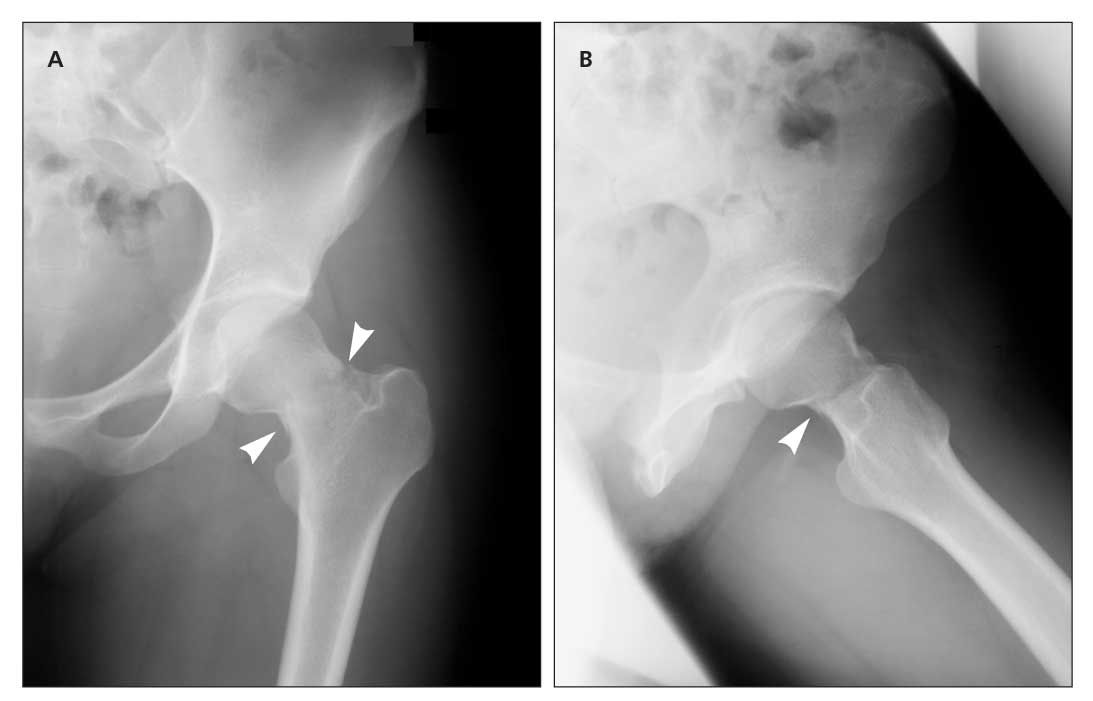

Radiology Quiz 36631 Radiopaedia Org from prod-images-static.radiopaedia.org Stress fractures are tiny cracks in a bone. Wikipedia has a comprehensive definition thankfully, stress fractures in the large bones of the body are rare. You probably answered yes to a few questions that indicated you have one, and no to some that indicated you have. They're caused by repetitive force, often from overuse — such as repeatedly jumping up and down or stress fractures often occur in people who suddenly shift from a sedentary lifestyle to an active training regimen or who rapidly increase the intensity. Stress fractures occur over time, and it may be hard to know when the initial injury occurred. I've experienced stressful situations that bring my team together, and have seen some of our best work come from pressure. A fracture, or a broken bone, is a common consequence of falls and motor vehicle accidents. Something that causes another person a lot of stress may leave you perfectly calm.

How are stress fractures diagnosed?